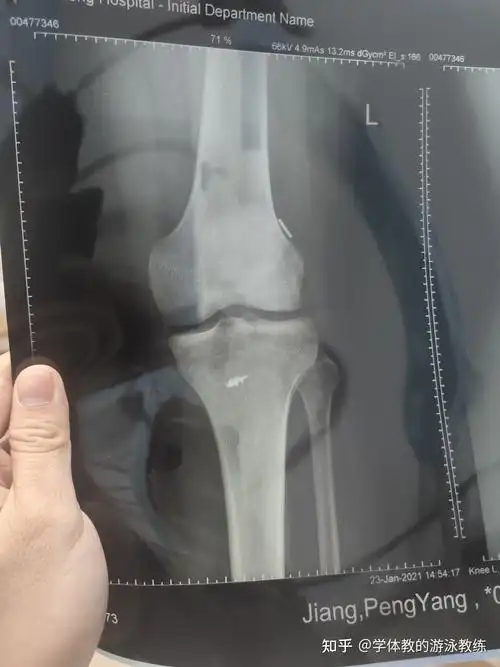

半月板损伤这个片子谁能看出来需要不需要

半月板损伤

左膝半月板损伤